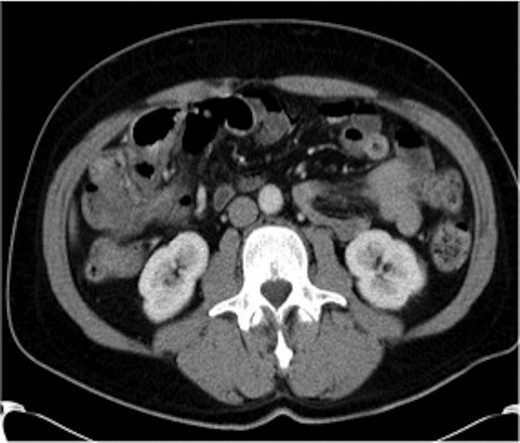

Haemoglobin was 14.9 g/dl and the white cell count (WCC) was 9 × 109/l. Other remarkable laboratory tests included a C-reactive protein (CRP) of 15 mg/l. Urinalysis was normal. The plain X-ray abdomen (AXR) (Fig. 1) revealed dilatation of a focal segment of large bowel with mildly dilated small bowel. Computed tomography (CT scan) of his abdomen reported that the gas-filled viscus is likely to represent the caecum (Fig. 2).

CT of the abdomen (Case 1) demonstrating the gas-filled caecum.